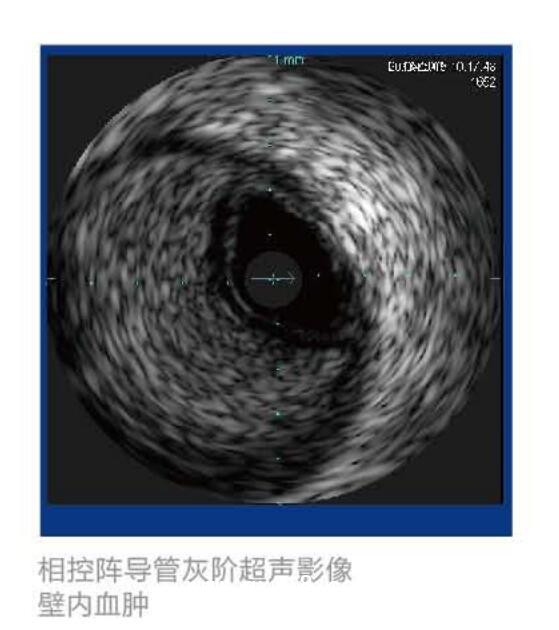

美國VOLCANO血管內(nèi)超聲波診斷儀 S5產(chǎn)品說明: